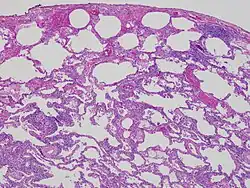

Lung biopsy

Lung biopsies can be diagnostic in cases of chronic hypersensitivity pneumonitis, or may help to suggest the diagnosis and trigger or intensify the search for an allergen. The main feature of chronic hypersensitivity pneumonitis on lung biopsies is expansion of the interstitium by lymphocytes accompanied by an occasional multinucleated giant cell or loose granuloma.[7][22]

When fibrosis develops in chronic hypersensitivity pneumonitis, the differential diagnosis in lung biopsies includes the idiopathic interstitial pneumonias.[23] This group of diseases includes usual interstitial pneumonia, non-specific interstitial pneumonia and cryptogenic organizing pneumonia, among others.[7][22]

The prognosis of some idiopathic interstitial pneumonias, e.g. idiopathic usual interstitial pneumonia (i.e. idiopathic pulmonary fibrosis), are very poor and the treatments of little help. This contrasts the prognosis (and treatment) for hypersensitivity pneumonitis, which is generally fairly good if the allergen is identified and exposures to it significantly reduced or eliminated. Thus, a lung biopsy, in some cases, may make a decisive difference.